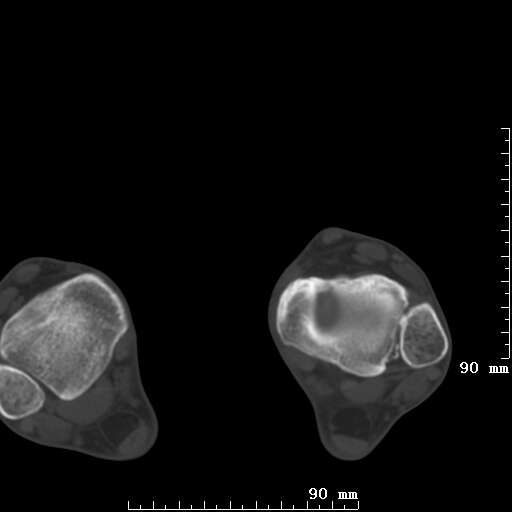

标题: CT19820:外伤一天,如何定性.男27Y [打印本页]

标题: CT19820:外伤一天,如何定性.男27Y

排除下创伤性关节炎吧,距骨有些囊变和硬化,周围韧带软组织有些机化、钙化。不是很像距骨无菌性坏死,感觉在关节面上的多,而不是距骨里面。

未见骨折及脱位像。距骨像是剥脱性软骨炎

支持!(踝关节距骨表面囊变和硬化 缺损)

距骨剥脱性软骨炎可能;踝关节创伤性关节炎?

未见明确新鲜骨折改变,距骨剥脱性软骨炎或踝关节创伤性关节炎可能。

关节周围多发高密度影,要结合病史